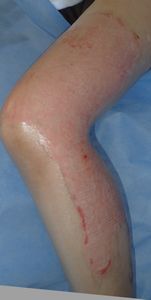

2016年2月19日,母から手渡された湯たんぽ(ゴム製)が破裂し,両手,両下肢に熱傷受傷。〇〇大学附属病院に救急搬送されて処置を受けたが,ベッドの空きがないため,△△病院に転送され形成外科に入院となった。ゲンタシン軟膏とフィブラスト,シリコンガーゼでの治療を受けたが,毎日処置をする医師が変わり,治療に対する説明は全く無く,おまけに処置の際に乱暴にガーゼを剥がされ,そのたびに激痛で,毎日の処置が憂鬱だった。3月2日に退院し,通院するように説明されたがもう治療を受けたくないため,ネットで熱傷治療について検索。

3月10日,当科受診。痛みで歩けず,車いすで診察室に入ってきた。右大腿のガーゼは除去できたが,左大腿〜下腿のガーゼが固着し,ガーゼが除去できなかった。そのため,ガーゼの上からたっぷりワセリンを塗布し,その上は穴あきポリ袋で被覆し,吸収シートで覆い,その状態で帰宅してもらった。

翌日,車椅子でなく歩いて診察室に。「帰宅してしばらくしたら痛みがなくなり,普通に歩けるようになりました」とニコニコ。ガーゼも痛みなく除去できた。以後は両足ともに「穴あきポリ袋+吸収シート」で治療。

| 右大腿内側 | 左下腿前面:ガーゼ固着 | 穴あきポリ袋で被覆 |